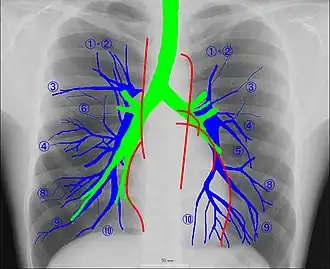

Рентгеноанатомия органов грудной клетки.

Рентгеноанатомия органов грудной клетки. Зелёным обозначены трахея и крупные бронхи, синим — ветви лёгочных артерий, красным — дуги тени сердца, цифрами отмечены сегменты лёгких.

При изучении рентгеноанатомии органов грудной клетки обращают внимание на рентгеновскую структуру видимых костей и мягких тканей грудной клетки; форму и прозрачность для рентгеновских лучей областей, на которые проецируется лёгочная ткань (так называемых «лёгочных полей»), а также их структуру, сформированную тенями сосудов лёгких («лёгочный рисунок»); расположение и структурность корней лёгких; положение, форму куполов диафрагмы и синусов плевральных полостей; форму и размеры тени средостения (в том числе сердца).

Лёгкие на рентгенограмме образуют лёгочные поля, располагающиеся по обе стороны от интенсивной тени средостения. Правое лёгочное поле короче и шире левого. В лёгочных полях различают верхушки (зоны выше ключиц), верхние отделы — от верхушек до передних отрезков вторых рёбер, средние отделы — между вторыми и четвёртыми парами рёбер, и нижние отделы — от четвёртых рёбер до диафрагмы. Лёгочные поля в норме очень светлые (тёмные на негативе) из-за высокой рентгенопроницаемости заполненной воздухом лёгочной ткани. Структура лёгочных полей называется лёгочным рисунком, анатомическим субстратом которого являются лёгочные сосуды и, в малой степени, лёгочный интерстиций. Лёгочный рисунок визуализируется в виде переплетения сосудистых теней тяжистого, округлого и овального вида, более интенсивных в местах их пересечений. В направлении от корней лёгких к периферии рисунок лёгочных сосудов становится беднее и совсем не визуализируется на расстоянии 1—1,5 см от края лёгочных полей. Лёгочный рисунок наиболее густой в нижних отделах лёгочных полей, обедняясь к верхушкам. Тени бронхов на рентгенограмме визуализируется в виде двойных полосок или колец с просветлением внутри.[3][4]

Корни лёгких.

Тень корней лёгких определяется парамедиастинально на уровне передних отрезков II—IV рёбер, левый корень располагается несколько выше правого и частично скрыт тенью средостения. Ведущим анатомическим субстратом в формировании тени корней лёгких являются лёгочные артерии и бронхи, в меньшей степени — лёгочные вены и другие структуры. В норме корни лёгких имеют неоднородное изображение, представляя собой структурированную совокупность элементов различной плотности. В корнях лёгких различают головку, тело и хвост. Правый корень визуализируется на всём протяжении в виде лентовидной, суживающейся книзу изогнутой тени средней интенсивности, отделённой от тени сердца промежуточным и нижнедолевым бронхами. К периферии от корней лёгких отходят лёгочные сосуды, причём артериальные ветви имеют более вертикальное направление, венозные — более горизонтальное. Ширина корня лёгкого соответствует ширине его основного артериального ствола; в норме она равна ширине бронха, отделяющего корень от средостения, и не превышает 1,5 см.[3][4]